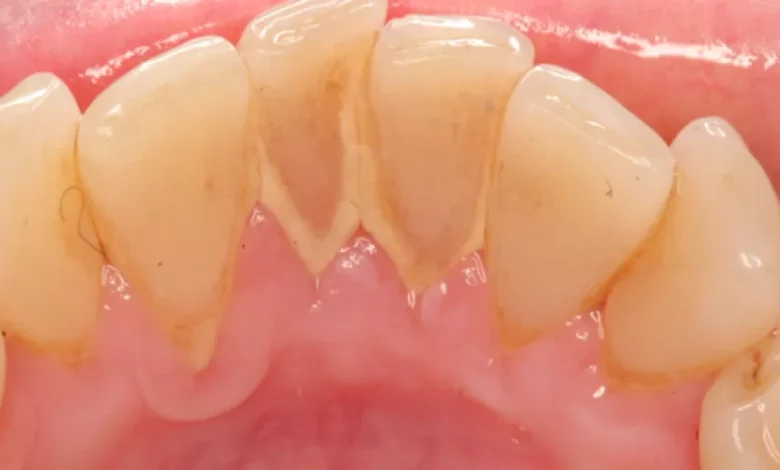

جير الأسنان هو طبقة صلبة صفراء أو بنية اللون تتكوّن بفعل تراكم البلاك، وهي البكتيريا المختلطة ببقايا الطعام على سطح الأسنان لفترة طويلة دون تنظيف فعّال. ومع مرور الوقت، يتحوّل هذا البلاك إلى جير لا يمكن إزالته بالفرشاة العادية، بل يبدأ في مهاجمة اللثة، والتسبب في نزيف مستمر، ورائحة فم كريهة، وقد يتفاقم الأمر إلى تآكل العظام المحيطة بالأسنان. لذلك، يُعد التخلص من الجير مسألة ضرورية ليس فقط من أجل المظهر، بل للحفاظ على صحة الفم بالكامل.

المشكلة أن كثيرًا من الناس لا يلاحظون بداية تشكّل الجير إلا بعد أن يصبح واضحًا ومزعجًا، خاصة في الجوانب الخلفية من الأسنان، وبين الفراغات التي يصعب الوصول إليها بالفرشاة. والأسوأ أن تجاهل هذه الطبقة يؤدي إلى ضعف تماسك الأسنان، وانحسار اللثة، مما يجعل العلاج أكثر تعقيدًا وتكلفة لاحقًا. ولهذا من الضروري التعامل مع الجير في مراحله المبكرة، والبحث عن طرق فعالة وآمنة لتنظيفه حتى في المنزل.